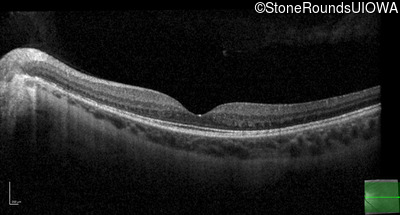

Optical Coherence Tomography - Right - 20/40 +1

Exemplar / OCT Stack